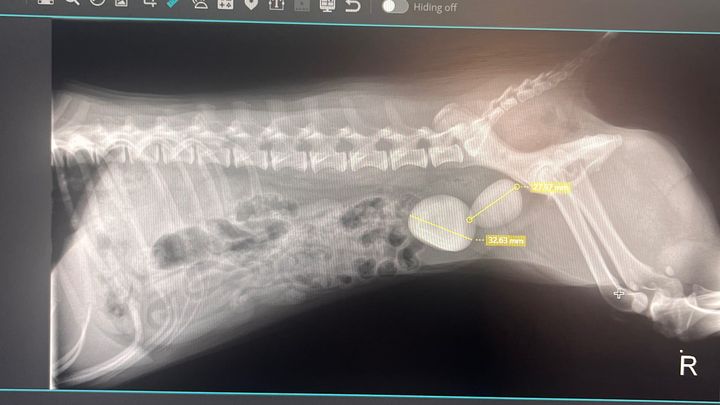

Hi, my name is Bella. I am a 6year old Maltese who was recently adopted on June 2024. I have a new loving home and family. After spending more time with my loved ones they noticed how sick I really am. Luckily my human noticed and took me to the hospital vet. Although I am spayed, I kept bleeding heavily. After running some test, they found two very large crystal stones in my bladder. I am in a lot of pain, have no control of my bladder and have not been myself lately. Please help my human get me to surgery as soon as possible so I can get back to wagging my tail enjoying my new life. With lots of paw love - Bella.